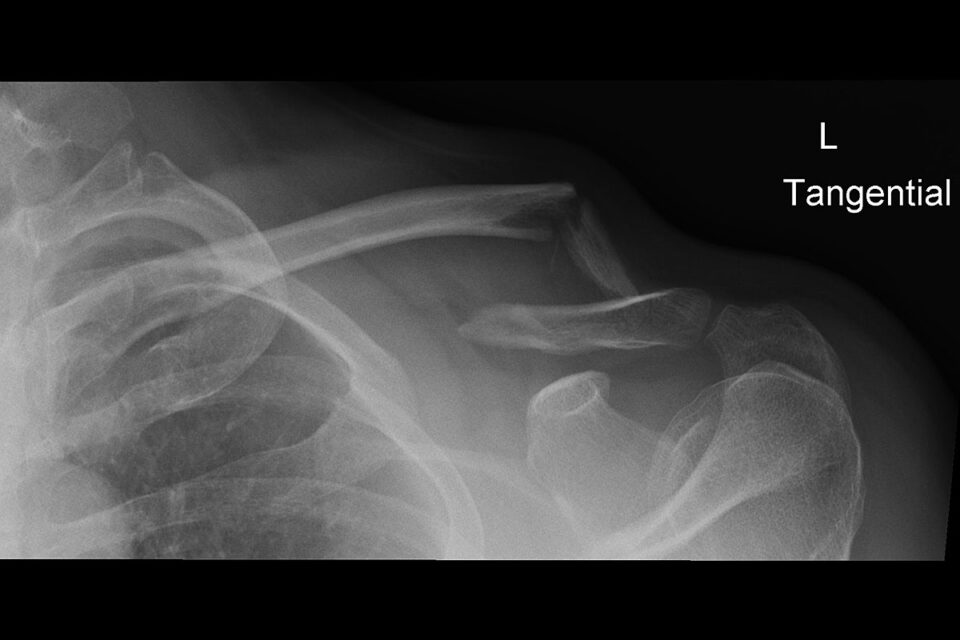

Manchmal geht es schnell, auch wenn man nicht «schnell» fährt.2022 stand von einem Tag auf den andern die persönliche Genesung im Vordergrund. Nach einem Skiunfall am 23.03.2022 musste ich einige Aufträge verschieben oder sogar absagen.Dank meiner erweiterten Unfallversicherung konnte ich mich auf die Physiotherapie und medizinische Trainingstherapie konzentrieren und dennoch alle wichtigen Rechnungen bezahlen. Nun…